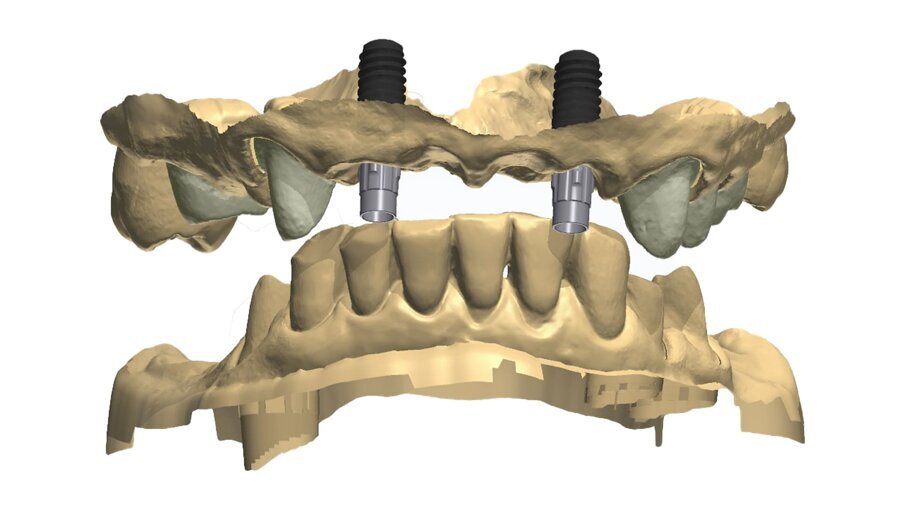

I dati raccolti sono molti ma la procedura digitale consente di sommarli e confrontarli senza limiti e indicando le possibili migliori e correzioni lungo il percorso. Dopo un breve periodo di condizionamento dei tessuti (Fig. 30) rileviamo l’impronta master per la finalizzazione ultima della riabilitazione protesica. L’impronta degli elementi naturali viene rilevata posizionando dei fili detrattori secondo la tecnica del doppio filo mentre per gli impianti verranno usati gli scan body dedicati (Fig. 31). Le potenzialità digitali consentiranno di avere una stabile lettura della posizione di centrica rilevandola prima della rimozione dei provvisori e sovrapponendola a provvisori rimossi (Fig. 32). In laboratorio l’odontotecnico realizza i modelli (Figg. 33, 34) sovrappone le immagini (Fig. 35) e raccoglie gli elaborati dei vari passaggi che porteranno alla finalizzazione del progetto digitale (Figg. 36, 37). Gli impianti in Zirconia non offrono molte soluzioni protesiche, è importante che il loro posizionamento tenga conto di quest’aspetto mettendo l’odontotecnico nelle condizioni più favorevoli (Fig. 38). Questa sistematica prevede l’uso di un moncone in titanio cementato nella struttura protesica che permette l’avvitamento all’interno dell’impianto. Nella connessione implantare è presente un’intercapedine dove alloggia il collarino in titanio del T-base totalmente inglobato all’interno della zirconia, evitando comunicazioni coi tessuti adiacenti. Va comunque considerato l’aspetto tecnico importante legato allo spessore della struttura in zirconia che deve avvolgere l’intero moncone in titanio. (Fig. 39, 40).

Fig. 34_Dettaglio del modello superiore con la visione palatale, con i monconi t-base da ancoraggio per elementi CAD/CAM.

Fig. 35_Sovrapposizione di un’immagine stilizzata degli elementi realizzabili con un margine muso ricreato.

Fig. 38_Il ponte tra gli impianti in Zirconia rappresenta un progetto complesso tra il rispetto del tunnel mucoso, l’anatomia vestibolare, gli spazi circolari e il foro per l’avvitamento coronale.